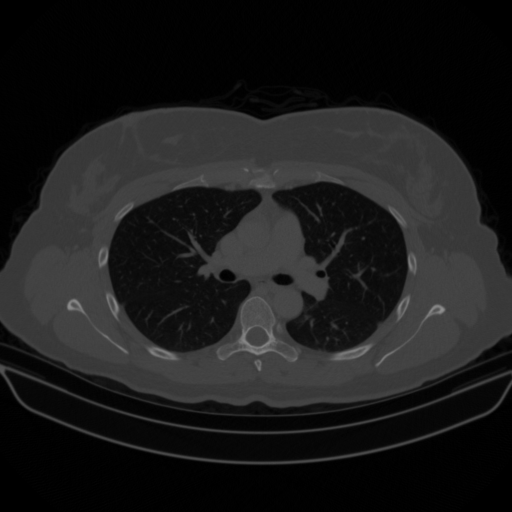

Original NATIVE CT scan (input)

Full window (WL 1023.5, WW 4095 β†’ Low βˆ’1024, High +3071)

Lung window (WL -600, WW 1500 β†’ Low βˆ’1350, High +150)

Mediastinum window (WL 40, WW 400 β†’ Low βˆ’160, High +240)